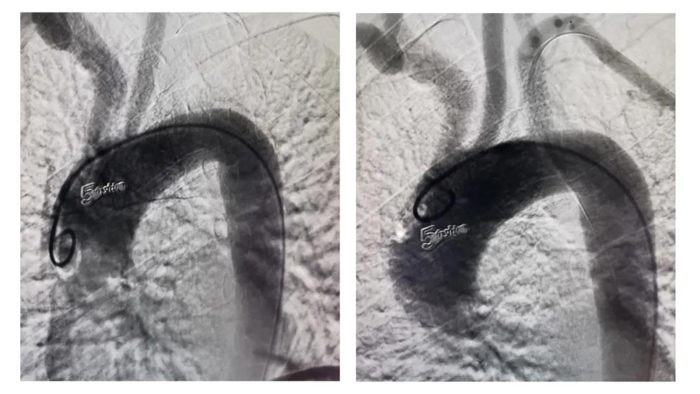

術(shù)前、術(shù)后造影對比圖

在血管外科徐存東主任的指導(dǎo)下,李強主治醫(yī)師作為術(shù)者參與此次手術(shù)的開展。術(shù)中造影證實,鎖骨下動脈起始段完全閉塞,長度>2cm,屬復(fù)雜病變。在嘗試順行開通無果后,果斷穿刺肱動脈,采用逆行入路開通。因?qū)е卵荛]塞的斑塊質(zhì)硬鈣化,在反復(fù)不氣餒地嘗試后,終于將導(dǎo)絲通過閉塞段,隨后對位精準(zhǔn)釋放支架。再次造影可見支架與血管壁貼合良好,前向血流通暢,左側(cè)椎動脈血流正向(TICI分級3級)。歷經(jīng)兩個半小時,手術(shù)順利完成?;颊咝g(shù)后隨即感覺左上肢知覺恢復(fù),麻木感減輕,頭暈癥狀緩解。術(shù)后兩天治愈出院。